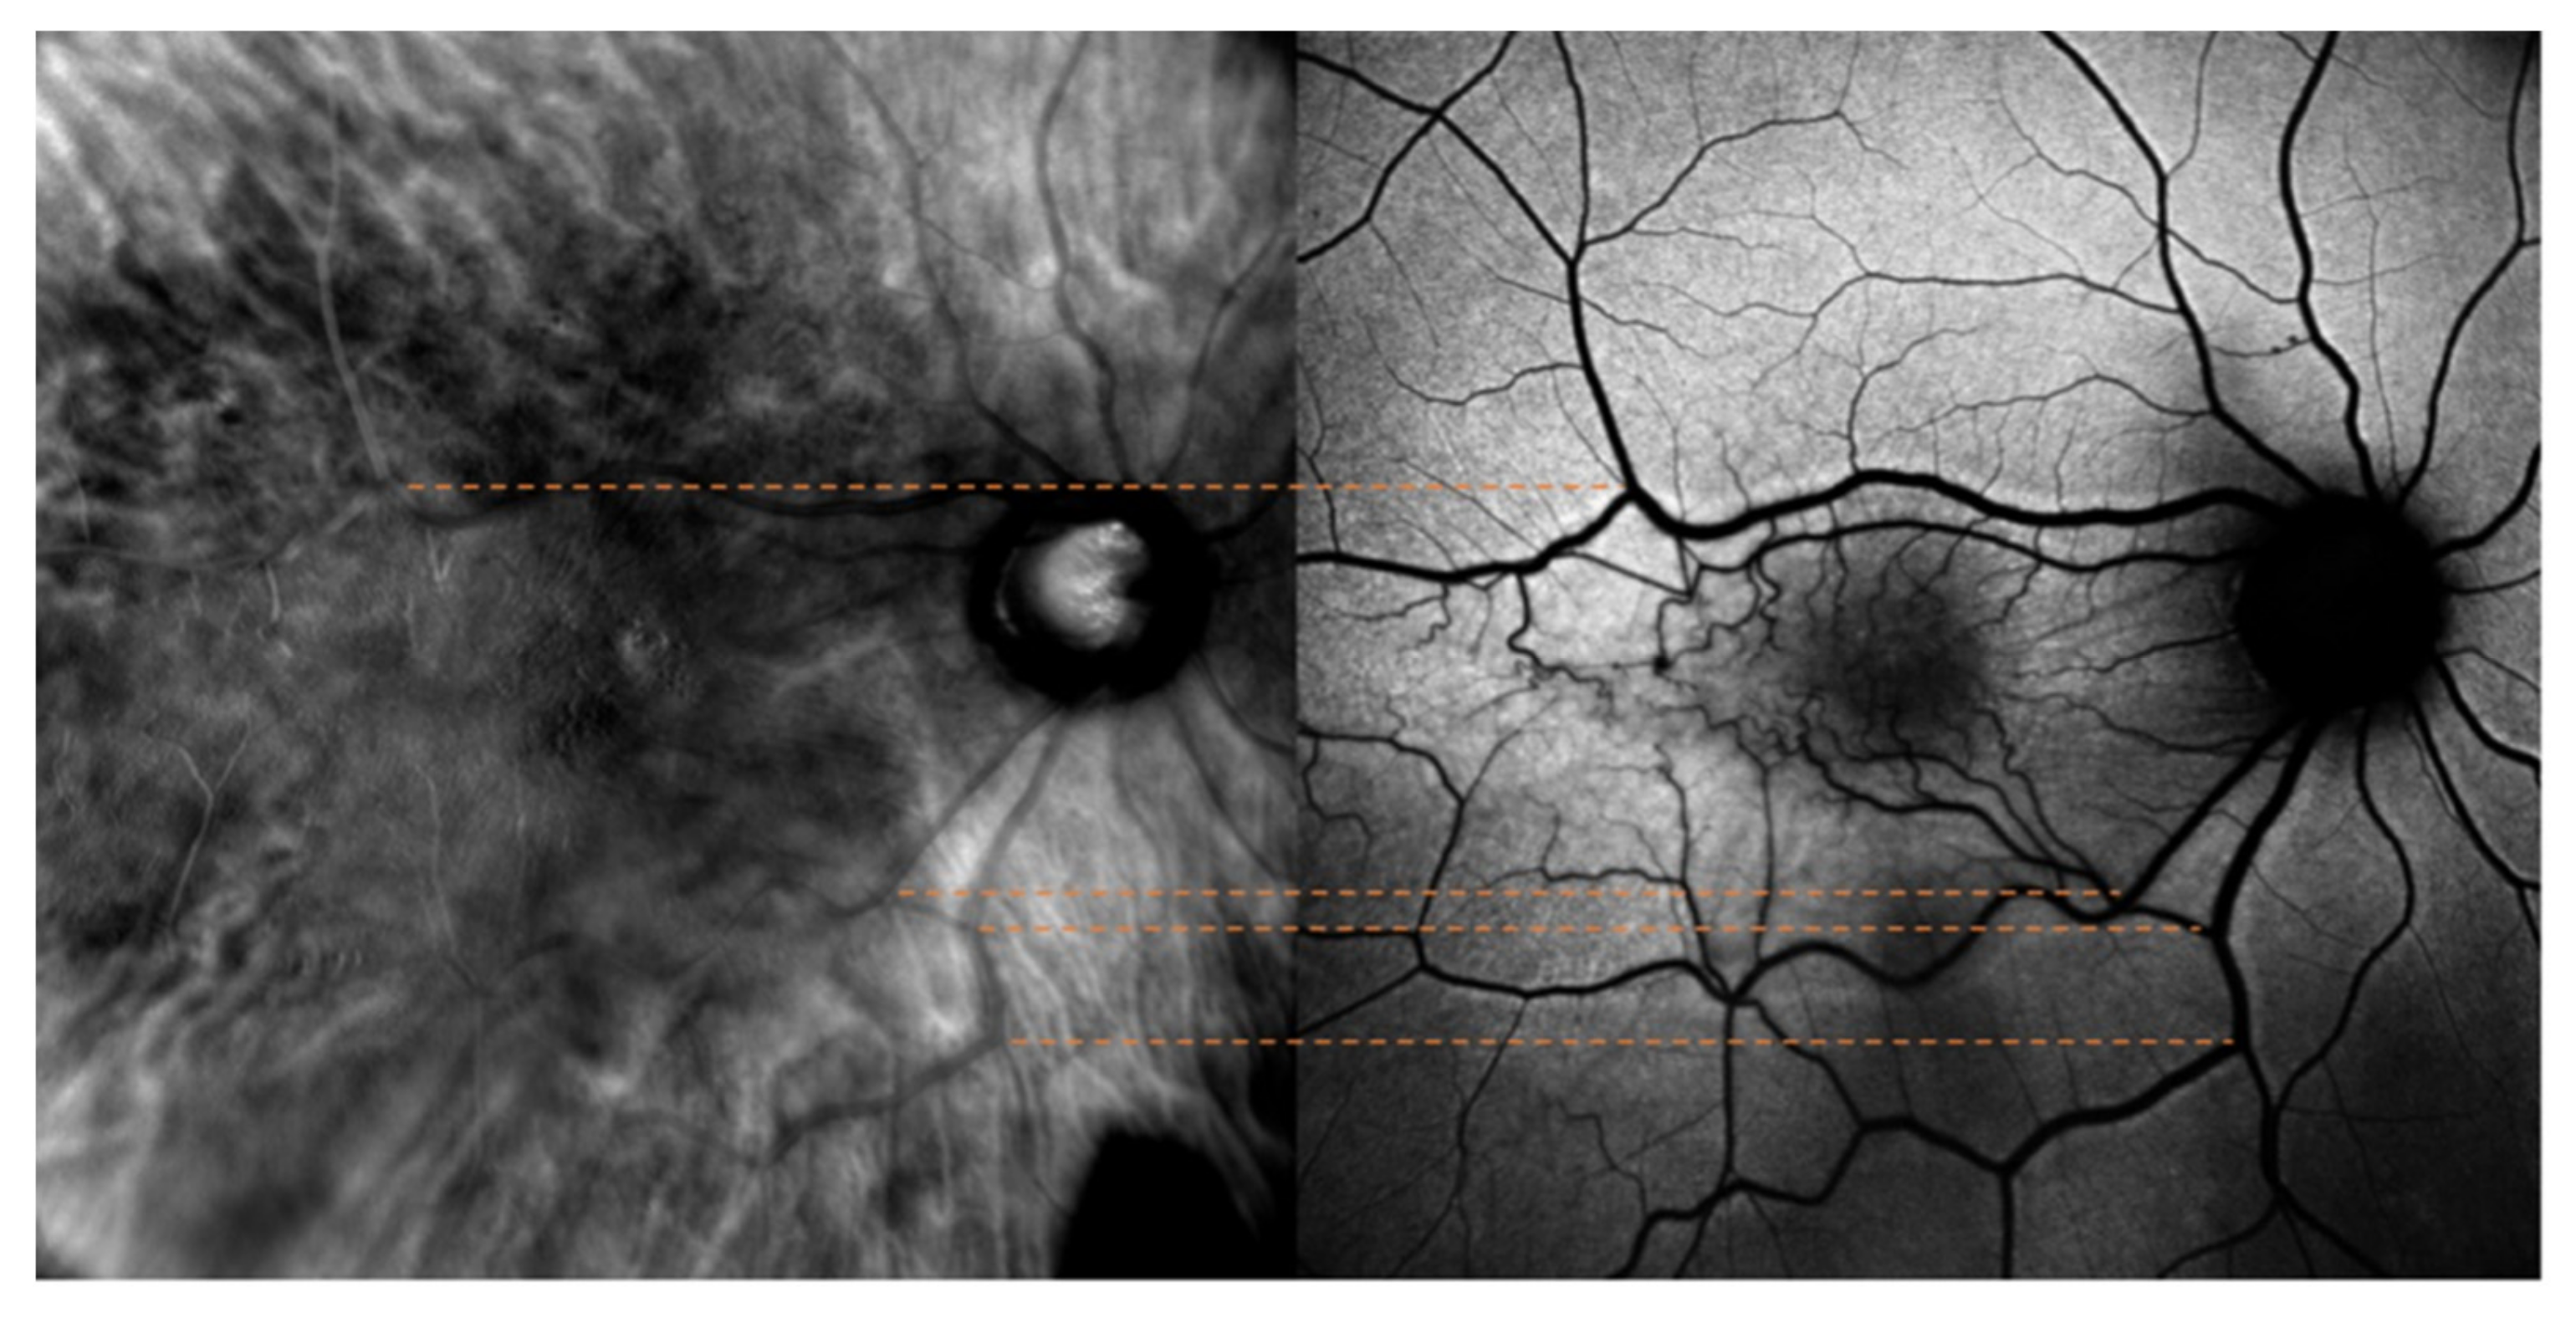

The optic nerve’s superior and inferior margins and retinal blood vessels on color fundus photography (blue lines and orange lines, respectively) were matched with their counterparts identified on retromode images, as shown in Figure 1. On the other hand, while FAF images were matched to retromode images using the retinal blood vessels alone (orange lines Figure 2), for OCT B-scans we used both the neuroretinal rim (grey lines) and the extension of the ERM itself. Particularly, the ERM margins on OCT images were projected onto the retromode image through orange lines, whereas black lines parallel to those originating from the neuroretinal rim were used to project the cystic spaces identified on OCT B-scans to their retromode counterparts (Figure 3).

Figure 2. Retromode and fundus autofluorescence (FAF) correspondence: blood vessels on FAF scan (orange lines) are used as reference points to check for appropriate image matching.